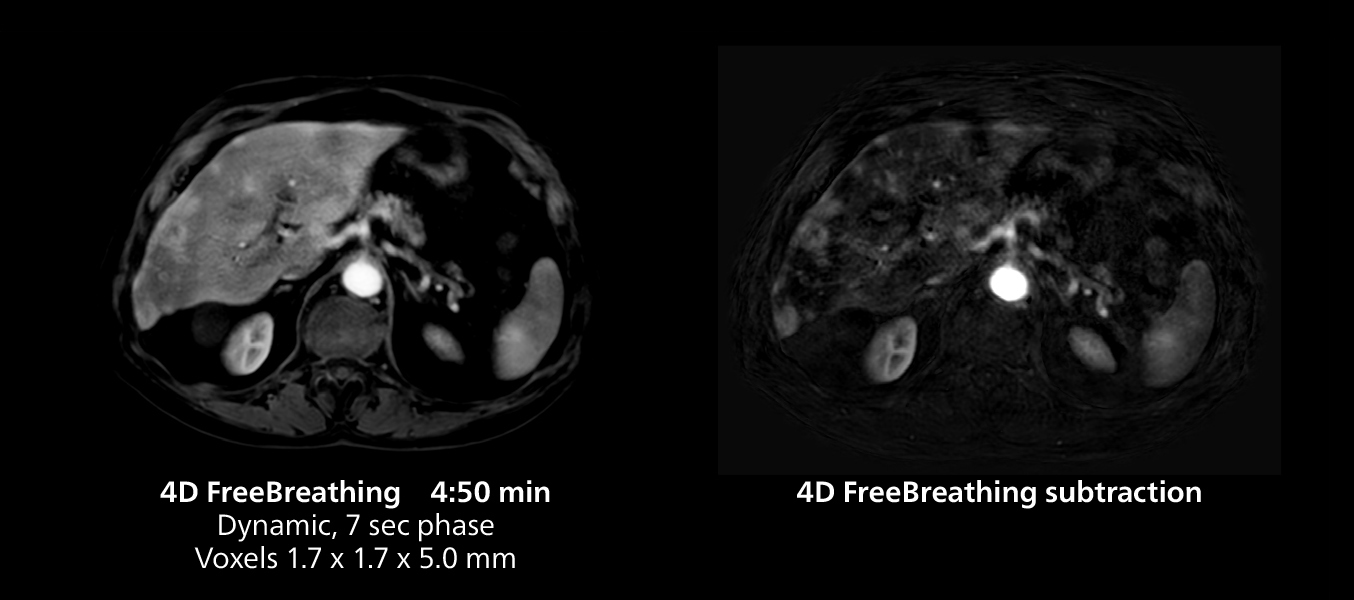

Liver imaging using MR 5300

This case includes 3D free breathing and 4D dynamic free breathing MRI of a metastasized liver. A high quality fatsat sequence with good resolution is obtained in 1:36 minutes with T2-weighted MultiVane XD.

Liver imaging using MR 5300

This case includes 3D free breathing and 4D dynamic free breathing MRI of a metastasized liver. A high quality fatsat sequence with good resolution is obtained in 1:36 minutes with T2-weighted MultiVane XD.

Free-breathing scans provide reproducibility and patient comfort

Dr. Gellée highlights the robust free-breathing scans as “the feature that makes the biggest difference in my daily work. The 3D free breathing sequences are very reproducible, and the axial acquisition is very good. For example, in endometriosis, which is one of my focus areas, it provides high contrast and good resolution so that I can see small details. We also use free breathing for liver and pancreas imaging. In multi-phase liver studies, 4D Free Breathing delivers 3-second temporal resolution, making a dynamic scan with more than one arterial phase possible.”

She also uses free breathing with 3D mDIXON to obtain in-phase, water and fat images in a single scan. “It is very reproducible before and after gadolinium, which makes it useful for liver imaging,” she adds.